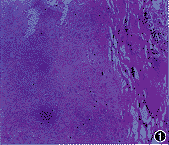

2. 组织病理学检查:11例分别取耳屏(10例)、喉、气管(3例)软骨活组织检查,见软骨细胞退行性变、溶解,软骨基质液化形成微囊及裂隙(图1)。PAS染色见软骨细胞退行性变,软骨基质液化形成微囊,其间可见增生的软骨细胞巢(图2)。Alcian 蓝染色显示软骨基质中酸性粘多糖含量减少。6例透射电镜下见胞核浓染,细胞质内细胞器不清,出现脂质空泡及囊状,并见许多溶酶体,细胞呈退行性变(图3)。

图1 软骨细胞退变,软骨基质液化形成微囊腔及裂隙,一侧可见软骨膜纤维增生。HE ×200 图2 软骨细胞退变,软骨基质液化形成微囊,其间可见增生的软骨细胞巢。PAS ×200 图3 软骨细胞退行性变,胞核浓染(N),细胞器不清,出现脂质空泡(B)及囊状,并见许多溶酶体(S)。×20000